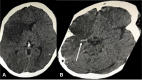

Case presentation: A 37-year-old Ugandan woman was diagnosed with HIV infection 8 days prior to her referral to our center. She was antiretroviral naïve. Her chief complaints were worsening cough, difficulty in breathing, fever and altered mental status for 3 days with a background of a 1-month history of coughing with associated drenching night sweats and weight loss. The reverse transcriptase-polymerase chain reaction for SARS-CoV-2 of her nasopharyngeal swab sample was positive. Chest radiograph demonstrated military pattern involvement of both lungs. The serum and cerebrospinal fluid cryptococcal antigen tests were positive. Urine lipoarabinomannan and sputum GeneXpert were positive for Mycobacterium tuberculosis. Computed tomography of the brain showed a large acute ischemic infarct in the territory of the right middle cerebral artery. Regardless of the initiation of treatment, that is, fluconazole 1200 mg once daily, enoxaparin 60 mg, intravenous (IV) dexamethasone 6 mg once daily, oral fluconazole 1200 mg once daily, IV piperacillin/tazobactam 4.5 g three times daily and oxygen therapy, the patient passed on within 36 hours of admission.